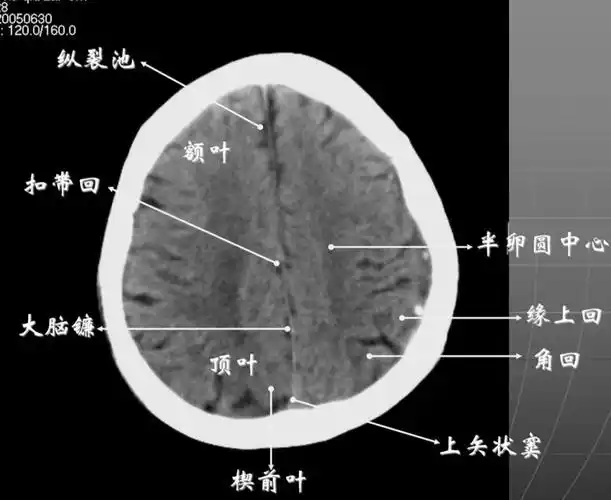

头颅ct 解剖图谱,人手一份

影像医生必须掌握的头颅ct解剖与常见出血梗死判读